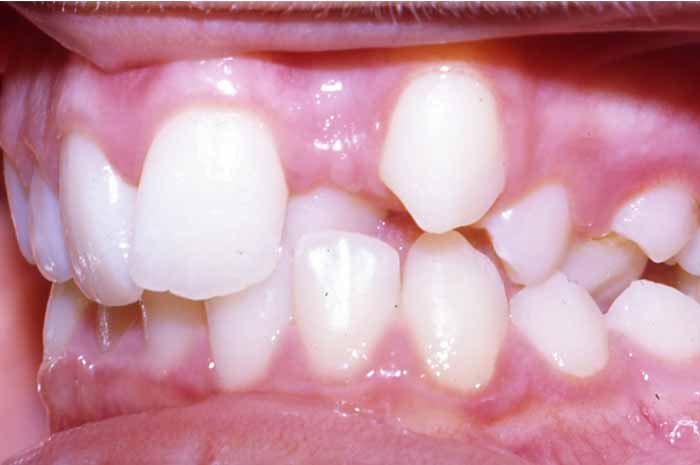

Problema:

Mordida cruzada anterior

Uno o varios incisivos superiores se situan por detrás de los inferiores, pudiendo alterar el correcto cierre de la boca.

Antes y Después